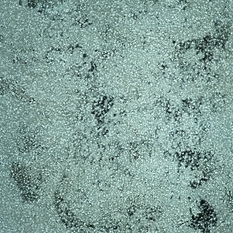

Pleomorphism, rather than polymorphism, characterizes a malignant lymphoma.

Condition/keywords: lymphoma, pleomorphism